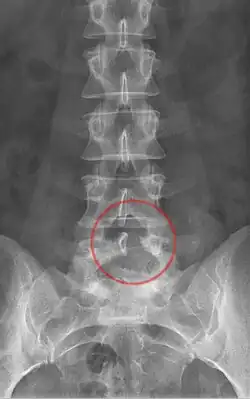

Die Laminektomie ist eine Operationsmethode an der Wirbelsäule. Dabei wird der Wirbelbogen mit dem Dornfortsatz bei einem oder mehreren Wirbeln entfernt, um Platz für eine Rückenmarks- oder Bandscheibenoperation zu gewinnen oder aber um einen zu hohen Druck, zum Beispiel auf Grund eines Tumors im Wirbelkanal, entlasten zu können. Oftmals wird sie auch bei der Spinalkanalstenose eingesetzt.

Da es durch diese Operation zu Instabilitätsproblemen der Wirbelkörper kommen kann, wird gelegentlich eine Wirbelkörperfusion, eine Spondylodese, ergänzt. Bei einer Laminektomie von einem oder zwei Bewegungssegmenten zeigte eine große randomisierte Studie an der Lendenwirbelsäule allerdings keinen Vorteil einer zusätzlichen Fusion der Wirbelkörper.[1] Bei längerstreckigen Laminektomie, wird wegen der Gefahr einer postoperativen Instabilität oftmals auch eine Fusion durchgeführt.

Bei einer Hemilaminektomie wird nach teilweiser Entfernung eines oder mehrerer Dornfortsätze lediglich eine Hälfte bzw. ein Teil des Wirbelbogens oder angrenzender Wirbelbögen zur Freilegung des Rückenmarks[2] entfernt.